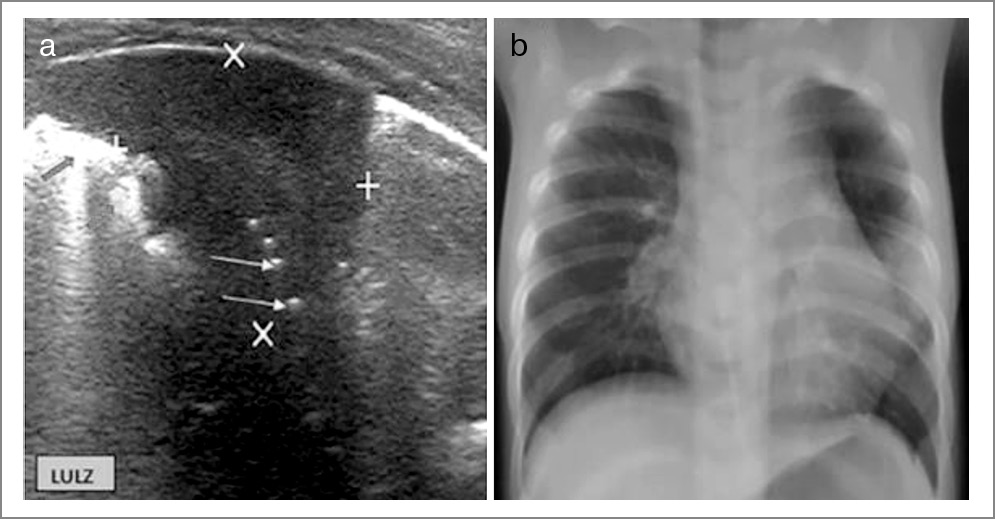

Ультразвуковое исследование (УЗИ) легких в последние несколько лет представляет все больший интерес для диагностики и динамической оценки пневмонии, плевритов (даже с небольшим объемом выпота), контроля проведения плевральной пункции [2]. У детей дошкольного возраста легочная масса мала, а грудная клетка тонкая, благодаря чему УЗИ легких может стать хорошей альтернативой стандартной рентгенографии ОГК в диагностике и последующем наблюдении за течением пневмонии. УЗИ легких показало высокую чувствительность и специфичность для диагностики пневмонии, а также возможность дифференцировать бактериальную и вирусную пневмонию [24, 25].

Так, по данным одной из публикаций зарубежных авторов, при анализе 200 пациентов с инфекционным поражением легких участки консолидации (0,5–1 см) обнаружены у 56 (28%) детей с бактериальным поражением легких (рис. 5). Большое количество В-линий и наличие интерстициального синдрома было характерно для вирус-индуцированных поражений легких (у 83 пациентов – 41,5%), а также сочетание зон консолидации и интерстициального синдрома (смешанная картина) замечено на УЗИ легких у 46 (23%) детей с микст-инфекцией (рис. 6) [26].

Рис. 5. Семимесячный мальчик с бактериальной ВП [26].

Рис. 6. Годовалый мальчик с вирусным поражением легких [26]: a – наличие субплеврального гипоэхогенного уплотнения размерами 3,5×2,5 см в правой нижней передней части с линейными/точечными эхогенными очагами (желтые стрелки), представляющими сонографическую воздушную бронхограмму; b и c – признаки интерстициального поражения также включают небольшое округлое субплевральное уплотнение (красная стрелка) и множественные очаговые В-линии (желтые стрелки) в левом нижнем боковом сегменте.

На рис. 6 видны консолидация размерами 2,8×2,3 см с точечной сонографической воздушной бронхограммой (желтые стрелки) и знаком разрыва (красные стрелки) в левом верхнем сегменте и участок консолидации в левом среднем сегменте, что характерно для бактериальной пневмонии. По лабораторным данным отмечались лейкоцитоз до 21×109 и повышенный уровень СРБ. Ребенок получал АБТ и был выписан на 8-е сутки.